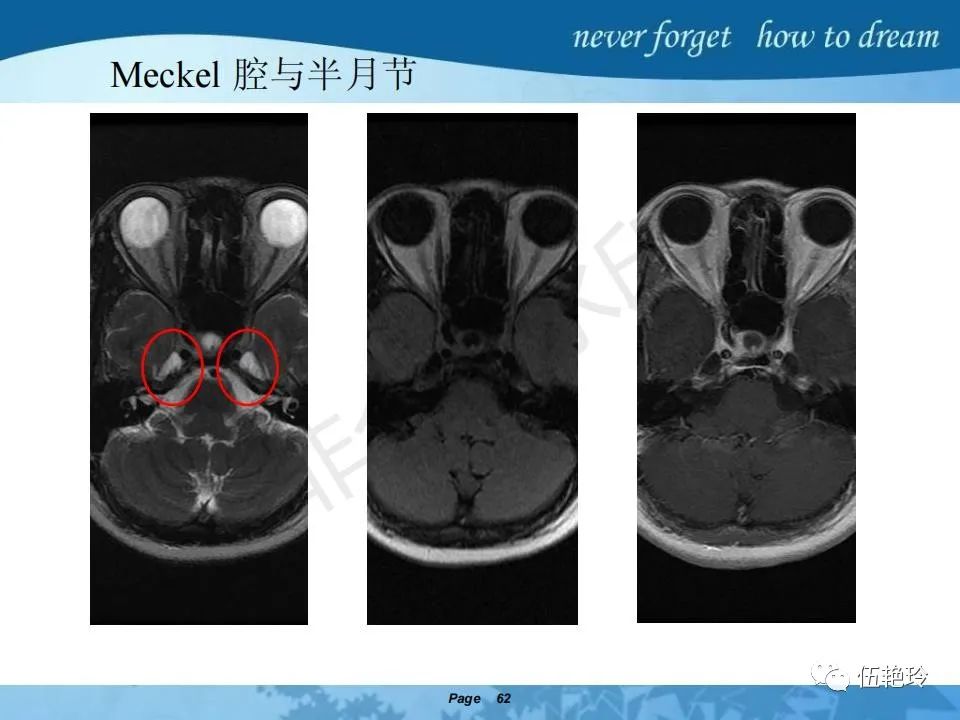

海绵窦区的解剖结构与鼻咽癌侵犯

2.31 向上颅内:①鼻咽顶壁→破裂孔(岩尖、斜坡)→蝶窦、海绵窦;②鼻咽顶壁→蝶骨基底部→蝶窦、海绵窦;③鼻咽侧壁→茎突前间隙→蝶骨大翼(卵圆孔)→海绵窦;④鼻咽侧壁→茎突前间隙→翼腭窝→ 颞下窝;⑤鼻咽前壁→鼻腔→翼突、翼腭窝→眶下裂→眶尖→海绵窦;⑥鼻咽前壁→鼻腔→上颌窦、筛窦;